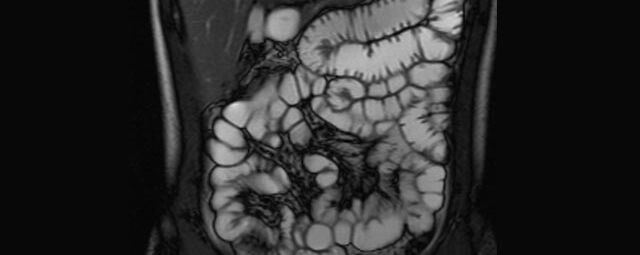

Sellink

• Dünndarm/Dickdarm

• Chronisch-entzündliche Darmerkrankungen wie Morbus Crohn oder Colitis ulcerosa. Beurteilung der Ausdehnung der Entzündung, Darstellung von Fisteln oder Abszessen bzw. einer Passagebehinderung (MR-Sellink, MR-Kolonographie, beide Untersuchungen nach spezieller Vorbereitung)

• Darstellung bzw. Kontrolle im Verlauf bei perianalen Fisteln und Abszessen

• Verlaufskontrolle des Lokalbefundes nach Rektumentfernung bei Karzinom